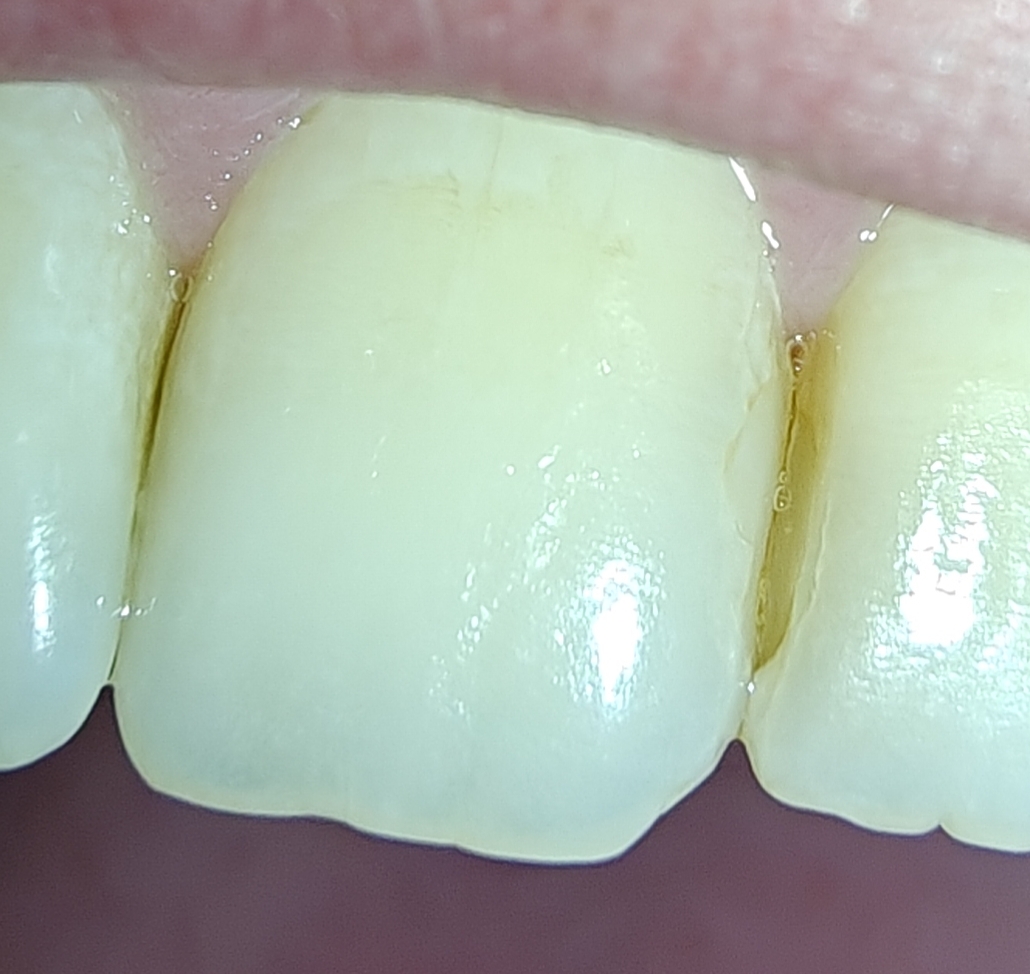

1.jpg 55Кб, 322x577

322x577

2.jpg 48Кб, 322x577

3.jpg 46Кб, 322x577

Ананасы подскажите пожалуйста

Сегодня ходил лечить пульпит, шестерку нижнюю, почистили каналы и поставили временную пломбу. Пломбу не фоткал как она была до. Было ощущение что при закрытии рта верхние зубы чуть-чуть опирались на зуб с пломбой, понял это уже только когда ебало от наркоза медленно начало отходить. Через четыре часа поел чуть теплого супчика с мягчайшими тефтельками, это был первый прием пищи после пломбирования, и понял что почему то верхние зубы снизу опоры больше не ощущают. Как будто часть пломбы отвалилась. Фотки прикрепляю.

Вопрос: насколько срочно надо бежать узнавать в порядке ли пломба или нужно перепломбировать? Этот же врач будет только восьмого, то есть через два дня. Сторонний специалист вообще в состоянии определить не нарушена ли правильность пломбы, если не он пломбировал?

Также: как они блять заебали. Известная клиника, полная запись на две недели вперед, врачи опытные все, сука каждый ебучий раз надо упрашивать чтобы они спилили так чтобы пломба не мешалась зубам. "Вот смотрите синюю бумажку вы покусали по ней видно что все нормально зубы друг другу не мешают." Ну это правда пока только на постоянных пломбах было, там как то менее стремно тк все равно просто кусок зуба отваливается, а тут интернет пишет про какую то инфекцию в каналы и прочий стрем если вдруг нарушена герметичность пломбы, а я вот смотрю и не ебу вообще герметична она там или нет внешне чет не определяется.